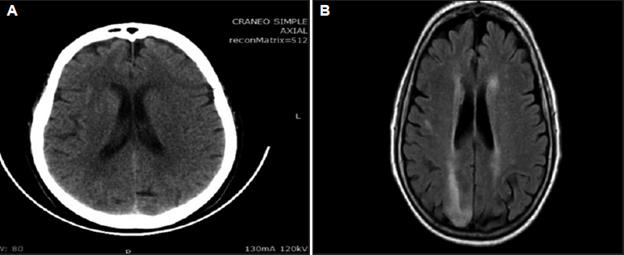

Antecedentes de hipertensión arterial, dislipidemia, obesidad, sedentarismo y episodios de cefalea bitemporal que en las últimas dos semanas se habían hecho más frecuentes e intensas. La cefalea era atribuida a crisis de migraña. Entre los medicamentos habituales utilizaba además del mencionado, losartán, hidroclorotiazida, atorvastatina y aspirina. Ante la sospecha de hemorragia intracraneana se procedió a practicar una TAC cerebral simple que fue normal (Figura 1A). La punción lumbar dio salida a un líquido cefalorraquídeo claro con una presión de 28 mmHg, 58 mg/dL de glucosa, 62 mg/dL de proteínas, linfocitos 3/mm3. No hematíes ni xantocromía.

Figura 1 A. TAC cerebral simple sin anormalidades estructurales. B. RMN cerebral simple. FLAIR. Zonas hiperintensas periventriculares y occipitales derechas.

Ante una TAC normal se procedió a una RMN cerebral simple que mostró zonas hiperintensas periventriculares y corticosubcorticales occipitales y otra pequeña a nivel parietal derecho y sin colecciones hemorrágicas. Secuencia Flair (Figura 1B).